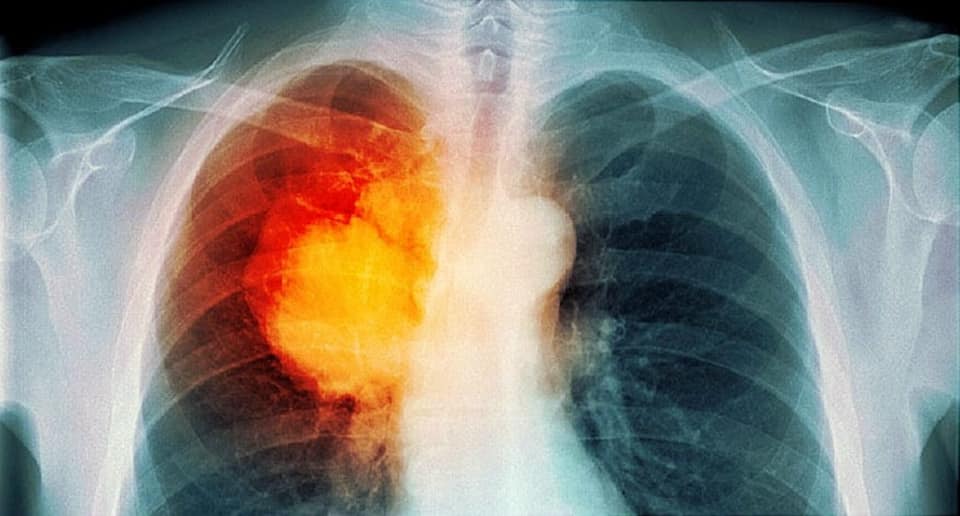

Tỷ lệ tử vong do ung thư phổi cao do bệnh thường được chẩn đoán vào giai đoạn tiến xa nên cần tăng cường hiệu quả hoạt động tầm soát, phát hiện sớm ung thư phổi. Gần đây, chụp cắt lớp điện toán xoắn ốc năng lượng thấp được chấp thuận như biện pháp tầm soát cho đối tượng nguy cơ cao (hút thuốc lá nhiều năm trên 30 gói/năm) giúp phát hiện nhiều hơn những bệnh nhân ung thư phổi giai đoạn sớm khu trú tại chỗ, tại vùng với kích thước u thường nhỏ hơn 7cm, có hoặc không có hạch rốn phổi cùng bên (giai đoạn I, II, IIIA). Với nhóm bệnh nhân giai đoạn sớm (khu trú tại chỗ tại vùng), điều trị triệt căn nhằm mục tiêu chữa khỏi: